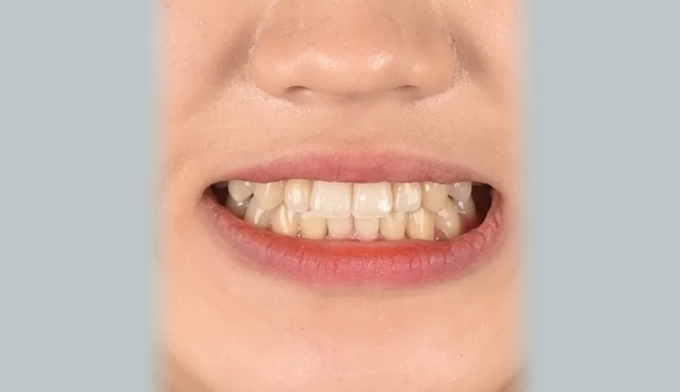

덧니뿐만 아니라 앞니의 교합이 좋지 않아 윗니가 아랫니를 덮지 못하는 개방교합도 동시에 나타납니다.

얇은 입술과 뒤로 들어간 입술을 가지고 있기 때문에 발치를 하지 않고 확장과 후방이동을 통해 최대한 공간을 마련하여 교정하기로 하였습니다.

원래 앞니의 길이가 위아래로 긴 형태를 가지고 있어서 치아의 길이를 조금 더 줄이면 보다 더 심미적이고 조화로운 형태를 나타냈을텐데, 환자가 치아의 형태를 바꾸길 원하지 않아 조금은 아쉬운 결과를 보입니다.

총 교정기간은 21개월입니다.